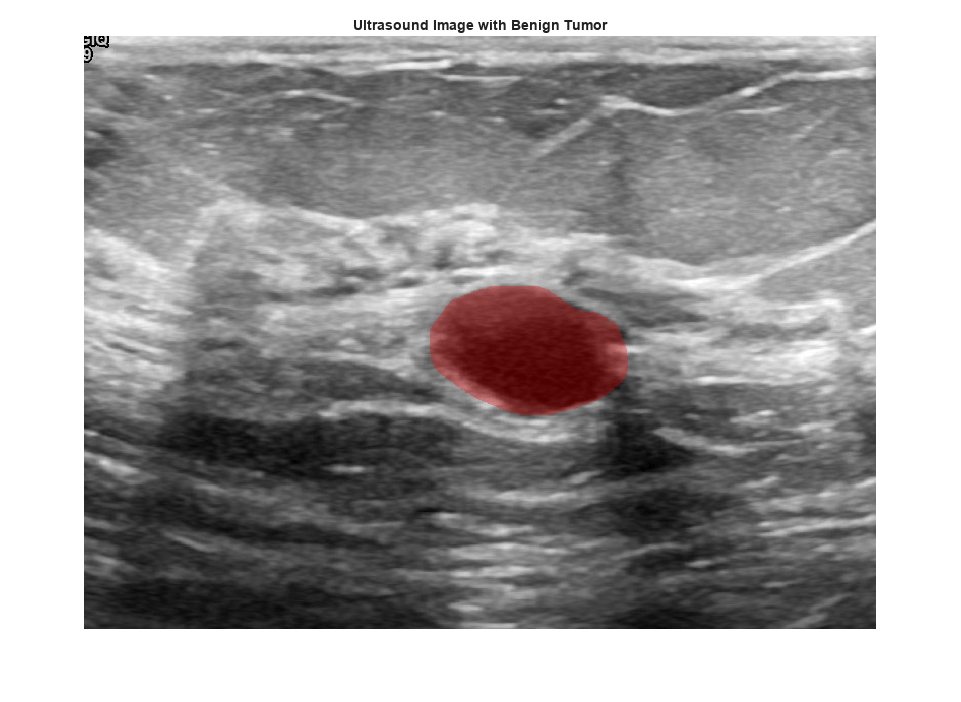

View an ultrasound image that contains a benign tumor with the tumor mask on the image.

benignIdx = find(imgds.Labels == "benign"); benignImage = readimage(imgds,benignIdx(146)); benignMask = readimage(maskds,benignIdx(146)); B = labeloverlay(benignImage,benignMask,Transparency=0.7,Colormap="hsv"); figure imshow(B) title("Ultrasound Image with Benign Tumor")